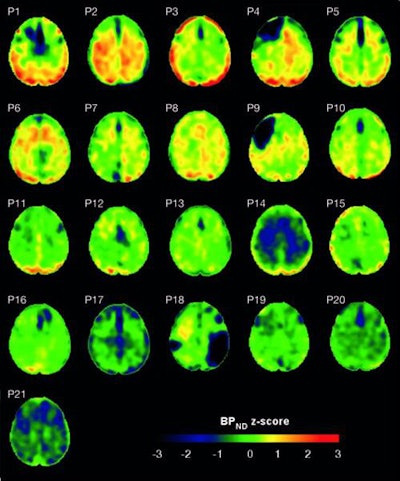

Flortaucipir nondisplaceable binding potential (BPND) z-score maps for each TBI patient are compared by voxel to healthy controls. TBI subjects are presented in descending order by number of voxels with flortaucipir BPND (z > 1.645). Patchy cortical and subcortical increase in tracer uptake is observed in some TBI participants, most consistently in the lateral occipital cortex (P1 to P8 and P10), while other TBI maps show similar BPND values as healthy control subjects (P17 to P21). Images courtesy of Gorgoraptis et al and Science Transitional Medicine.

Flortaucipir nondisplaceable binding potential (BPND) z-score maps for each TBI patient are compared by voxel to healthy controls. TBI subjects are presented in descending order by number of voxels with flortaucipir BPND (z > 1.645). Patchy cortical and subcortical increase in tracer uptake is observed in some TBI participants, most consistently in the lateral occipital cortex (P1 to P8 and P10), while other TBI maps show similar BPND values as healthy control subjects (P17 to P21). Images courtesy of Gorgoraptis et al and Science Transitional Medicine.The researchers also found evidence of a cognitive decline in MMSE scores (average, - 1.3; - 0.073 MMSE points per year) in the disabled TBI subgroup, compared with the good outcome TBI subgroup, which actually improved its collective MMSE scores (average, 1; 0.058 MMSE points per year), creating a statistically significant difference between the two subgroups (p = 0.041).